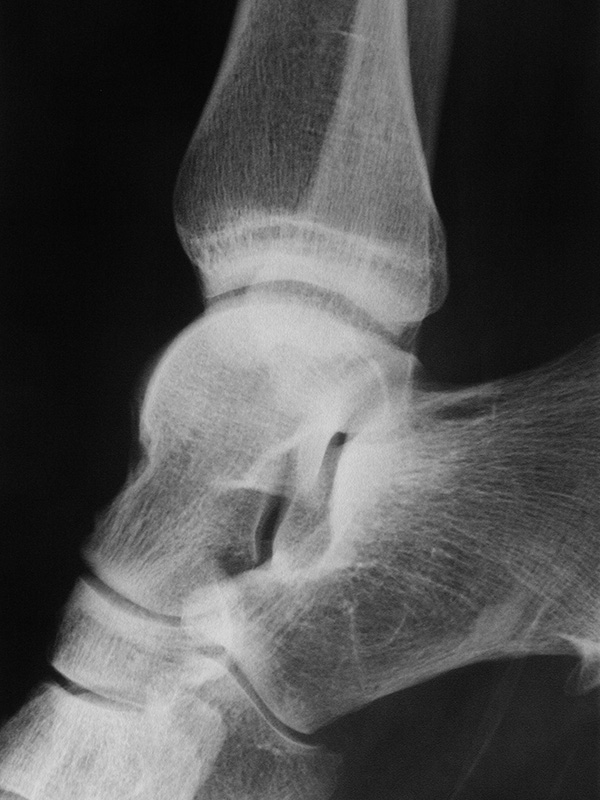

Sprunggelenk lateral ohne Belastung

Positionierung:

• Patient liegt auf dem Rücken und dreht den Fuß des aufzunehmenden Beins so nach innen, dass beide Malleolen genau übereinanderstehen.

• Die laterale Fuss-Seite liegt auf der Kassette, das Sprunggelenk ist 90° angewinkelt.

• Der Zentralstrahl wird zentral auf das Sprunggelenk gerichtet.

Kennzeichen des Röntgenbildes:

• Oberes und unteres Sprunggelenk sind rein seitlich abgebildet, inklusive Kalkaneus.

• Die Malleolen kommen übereinander zu liegen.

• Tibiagelenkfläche und Talusrolle werden exakt seitlich dargestellt, es kommt zu keinen Doppelkonturen.

• Die Fibula projiziert sich ins mittlere bis hintere Drittel der Tibiagelenkfläche.

• Die vordere und hintere Tibiakante, das Chopart-Gelenk und das Subtalargelenk kommen zur Darstellung.

• Das proximale Ende des Os metatarsale V ist mit abgebildet.

• Der Weichteilmantel (Achillessehne) ist erkennbar.

Besondere Bemerkungen zum Beispielbild:

• Patient mit anamnestisch chronischer OSG Instabilität.

• Ventral der Tibia findet sich ein abgebrochener Osteophyt.

Zur Vollansicht und zum Lesen der Bildbeschreibung bitte die Bilder anklicken.